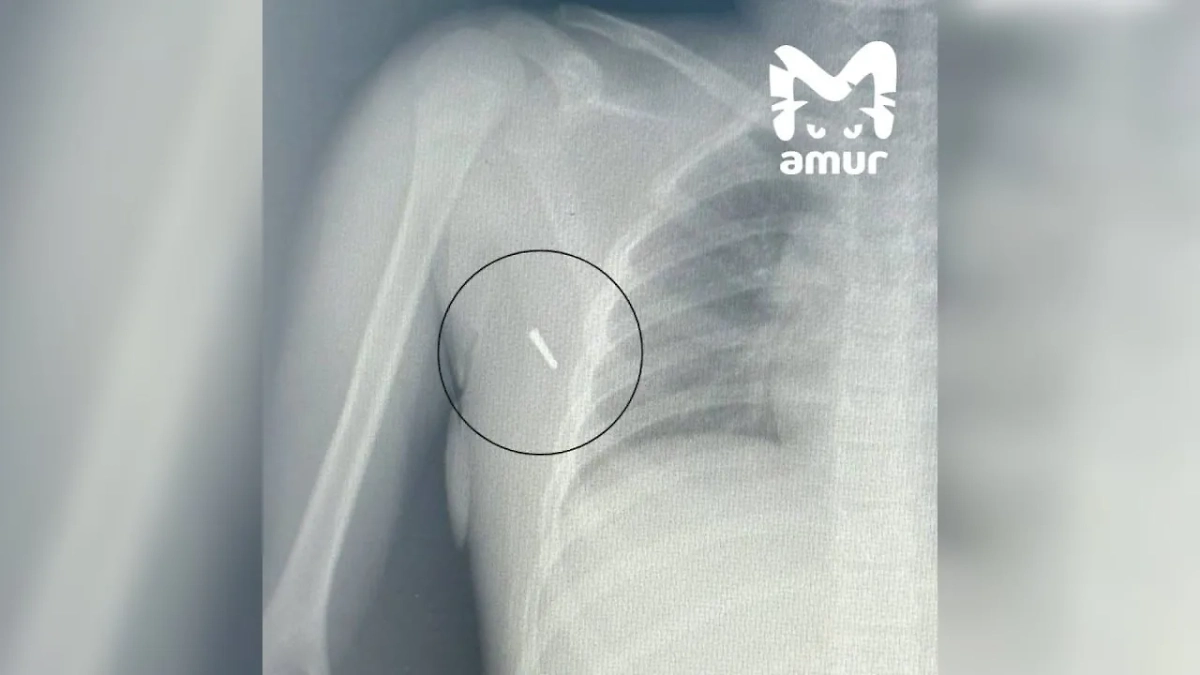

Рентгеновский снимок пострадавшей в Приморье. Фото © Telegram / Amur Mash

Восьмилетняя девочка получила травму во время ДТП в Артёме. В момент аварии она измеряла температуру. Термометр сломался, и его кончик вонзился в тело ребёнка. Пострадавшую срочно госпитализировали во Владивосток, где ей провели операцию. Через несколько дней реабилитации девочка вернулась домой.